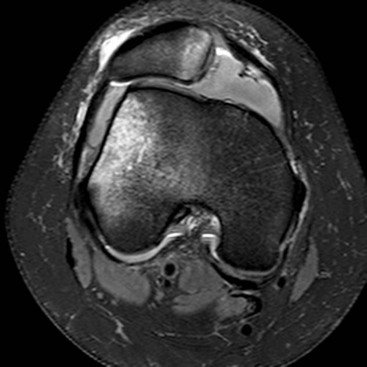

ACL tears are common sporting injuries. On MRI, complete tears appear as discontinuity of the fibres, increased signal and/or laxity (Fig. 46-49). The mid-substance of the ligament is injured more frequently than the proximal or distal portions. Partial tears or sprains of the ACL are recognised on MRI by altered signal and/or laxity in the presence of continuity of some fibres. There are several secondary imaging signs associated with ACL injury. Typically there is microfracture in the posterior aspect of the lateral tibial plateau and the subarticular lateral femoral condyle, reflecting impaction between these sites during subluxation of the knee at the time of the injury (pivot shift injury). ACL tears may be accompanied by anterior translation of the tibia relative to the femur. This can be detected on sagittal images as it will cause buckling of the PCL. The lateral notch sign, which is specific but not very sensitive for ACL injury, describes abnormally deep indentation of the condylopatellar sulcus of the lateral femoral condyle on a lateral conventional radiograph.30 ACL injuries are commonly associated with injury to other structures. O'Donaghue's triad describes tears of the ACL, MCL and medial meniscus. A Segond fracture, which has a high association with ACL injury, describes avulsion of a fracture fragment from the lateral margin of the lateral tibial condyle at the attachment of the joint capsule.